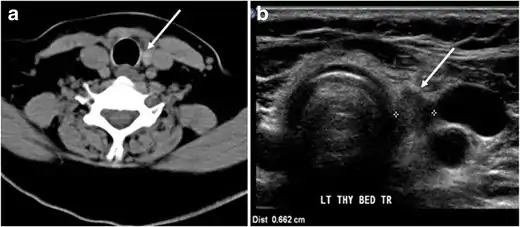

Fig. 7. A 51-year-old female patient post total thyroidectomy for PTC with elevated thyroglobulin measurement. an Axial non-enhanced CT scan of the neck at the level of the thyroid bed demonstrates a well-defined, rounded, homogenously dense soft tissue situated between the trachea and left internal jugular vein (white arrow). b Transverse ultrasound image of the neck demonstrates a well-defined, homogeneous, hypoechoic soft tissue nodule measuring 6 mm (white arrow) with no detected micro-calcifications. Biopsy showed a predominantly residual normal thyroid tissue with micro-foci of PTC.[1]